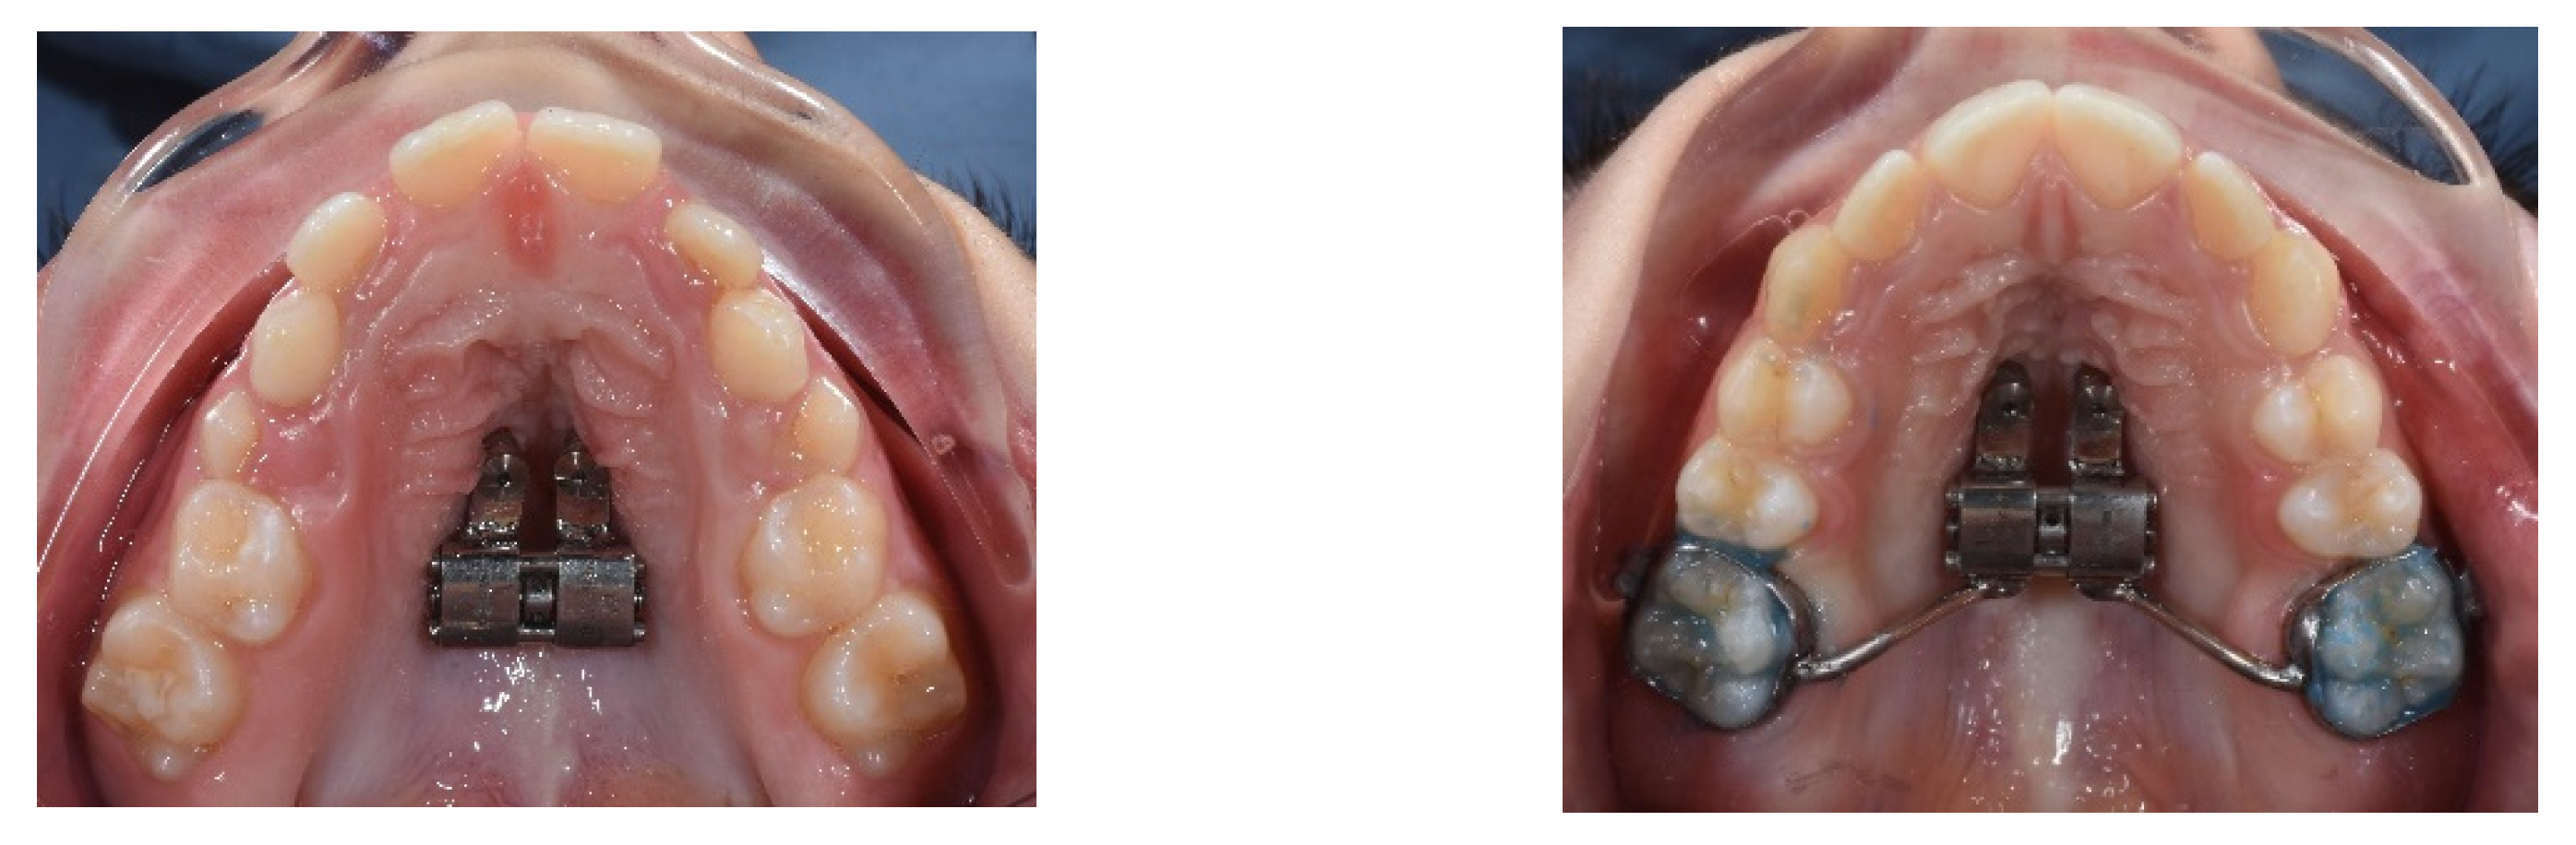

4. Case Report

4.1. Etiology and Diagnosis

4.3. Treatment Strategy

4.4. Treatment Progress